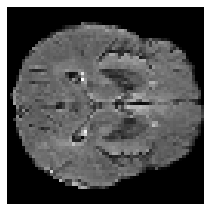

Disentangled representations can be useful in many downstream tasks, help to make deep learning models more interpretable, and allow for control over features of synthetically generated images that can be useful in training other models that require a large number of labelled or unlabelled data. Recently, flow-based generative models have been proposed to generate realistic images by directly modeling the data distribution with invertible functions. In this work, we propose a new flow-based generative model framework, named GLOWin, that is end-to-end invertible and able to learn disentangled representations. Feature disentanglement is achieved by factorizing the latent space into components such that each component learns the representation for one generative factor. Comprehensive experiments have been conducted to evaluate the proposed method on a public brain tumor MR dataset. Quantitative and qualitative results suggest that the proposed method is effective in disentangling the features from complex medical images.